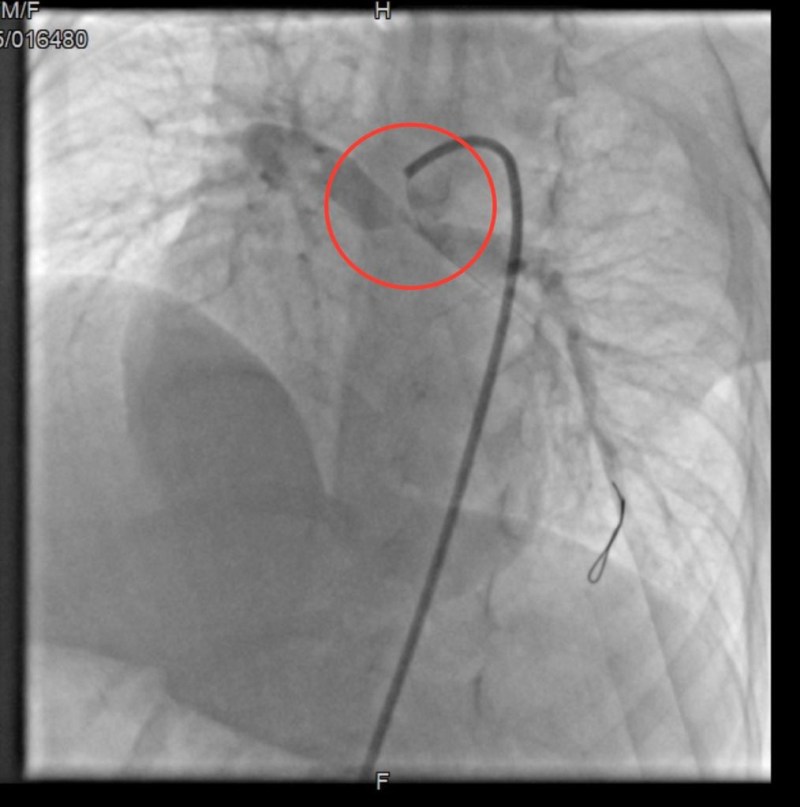

जोधपुर. अखिल भारतीय आयुर्विज्ञान संस्थान (एम्स) में तीन माह के शिशु को पेटेंट डक्टस आर्टेरियोसस (पीडीए) स्टेटिंग से जन्मजात ह्रदय रोग टेट्रोलॉजी ऑफ फ़ॉलो विथपल्मोनरी एट्रेसिया बीमारी से निजात दिलाई। इससे पहले इस अत्याधुनिक तकनीक से ऑपरेशन केवल दिल्ली एम्स में ही हो पाते थे। एम्स प्रशासन का दावा है कि राजस्थान में इस तरह का यह पहला ऑपरेशन है।

कई जगह दिखाने के बाद उसको कार्डियक सर्जरी की सलाह दी गई, परंतु अत्यधिक नीलेपन और पल्मोनरीआर्टरी की छोटी साइज के होने के कारण कार्डियक सर्जरी ज्यादा असरदार नहीं प्रतीत हो रही थी। तब कार्डियोलॉजी विभाग के डॉ. राहुल चौधरी और कार्डियोथोरेसिक और वैस्कुलर के डॉ. अनुपम दास ने मरीज को पीडीए स्टेंटिंग की सलाह दी।

शिशु का वजन कम होने, ऑक्सीजन सैचुरेशन का लेवल 70 प्रतिशत से नीचे होने एवं ऐसा प्रोसीजर पहली बार होने के कारण कॉम्प्लिकेशन की आशंका भी ज्यादा थी। दिल्ली एम्स की चिकित्सकों की सलाह एव टीम वर्क के फलस्वरूप ऑपरेशन सफल रहा। शिशु का वजन अब बढऩे लगा हैं। सैचुरेशन लेवल भी अब 85 प्रतिशत से ज्यादा ही रहता हैं।

आमतौर पर पीडीए जन्म के बाद बंद हो जाता है, परन्तु पल्मोनरी एट्रेसिया के मरीजों में ये बंद न होकर जीवनदायनी होता है। क्योंकि लंग्स को रक्त प्रवाह इसी के कारण होता है। पीडीए स्टेंटिंग के ऑपरेशन में इसमें स्टंट लगाकर इसे बंद होने से बचाया जाता है, ताकि ऑक्सीजन लेवल कम ना हो। यह ऑपरेशन छाती को बिना खोले पाव, हाथ या गले की आर्टरी में छोटा चीरा लगाकर किया जाता हैं।